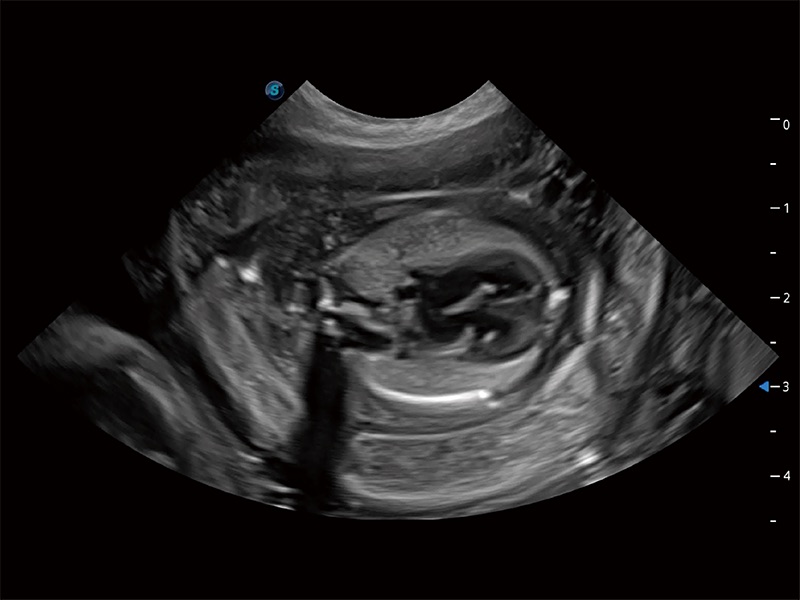

动物是人类最亲密的朋友和最值得信赖的伙伴。竞技宝(JJB)官方网站也一直致力于探索动物专用的超声影像解决方案。全新推出的ProPet系列,是竞技宝(JJB)官方网站在动物超声影像智能化、专业化、精准化的一次跨越式革新。动物不能用言语来表述自己的不适,通过超声影像,ProPet系列搭建了动物医生与不同物种沟通的“桥梁”,为动物医生注入了“治愈之力”。 ProPet 80 是竞技宝(JJB)官方网站匠心打造的一款高端动物专用彩超,采用性能卓越的全新硬件架构,极大提升超声系统的运行效率和数据处理能力,帮助动物医生从容应对日益增多的挑战性病例和日益多样化的临床需求。

高性能和先进的临床应用工具可以为动物医生提供临床信心。ProPet 80 搭载了先进的腹部和浅表应用工具,帮助医生在日常临床实践中发挥前所未有的作用。

ProPet 80 全新的动物超声智能软件和丰富的探头群,为动物医生提供了高清晰度和精细分辨率的图像,无论在宠物、马科、畜牧还是实验室动物等应用中都可以轻松应对,为您的日常工作带来满意的体验。